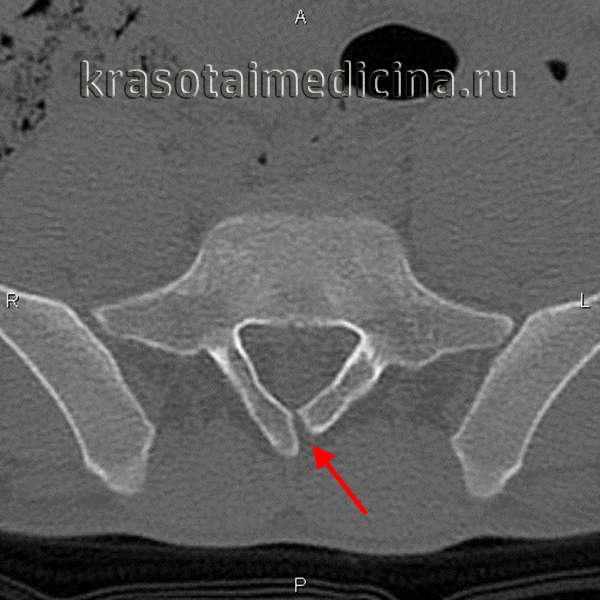

г) Фиксация концевой нити спинного мозга. Фиксация концевой нити или ее липома связаны с ФСМ из-за их предположительной герметичности. Герметичность терминальной нити и постоянное натяжение дистального спинного мозга не могут быть визуализированы. Диагностике фиксации терминальной нити могут способствовать только косвенные признаки, такие как низменное положение конуса, утолщение нити (липома нити), увеличение размера люмбального мешка, раздвоенные дужки.

У большинства пациентов диагноз ставится только после выполнения КТ. Показания к лечению остаются спорными, так как мнения экспертов расходятся. Хирургическое лечение фиксированной терминальной нити является простой и безопасной процедурой. Итоги отличные. Рефиксация маловероятна, а миелодисплазия отсутствует.